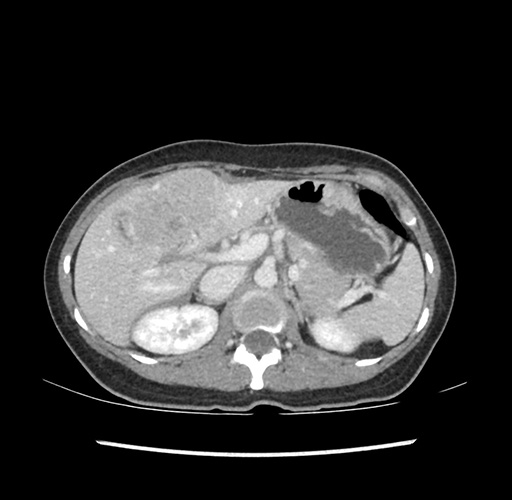

Imaging Analysis

Look through the patient's CT scan to identify any areas of concern for the necessary procedure.

Based on your CT findings, which issue(s) would give reason for "planned slowing down moment(s)" in this case?